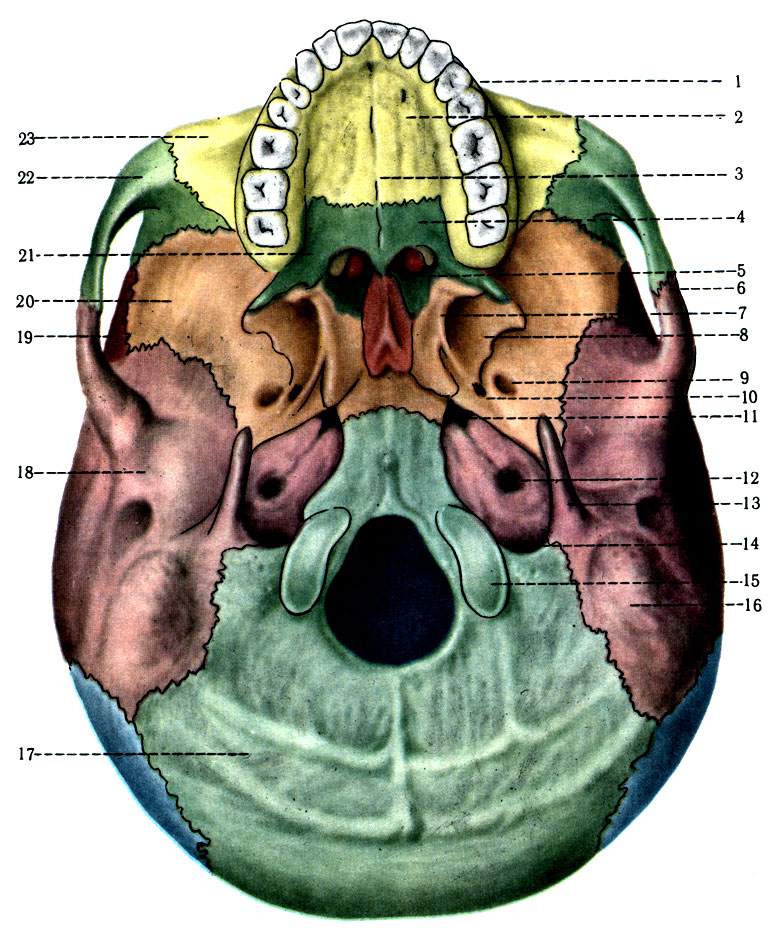

Анатомические детали: Фотографии топографии черепа с нижнего вида

Раздел: Альбом идей